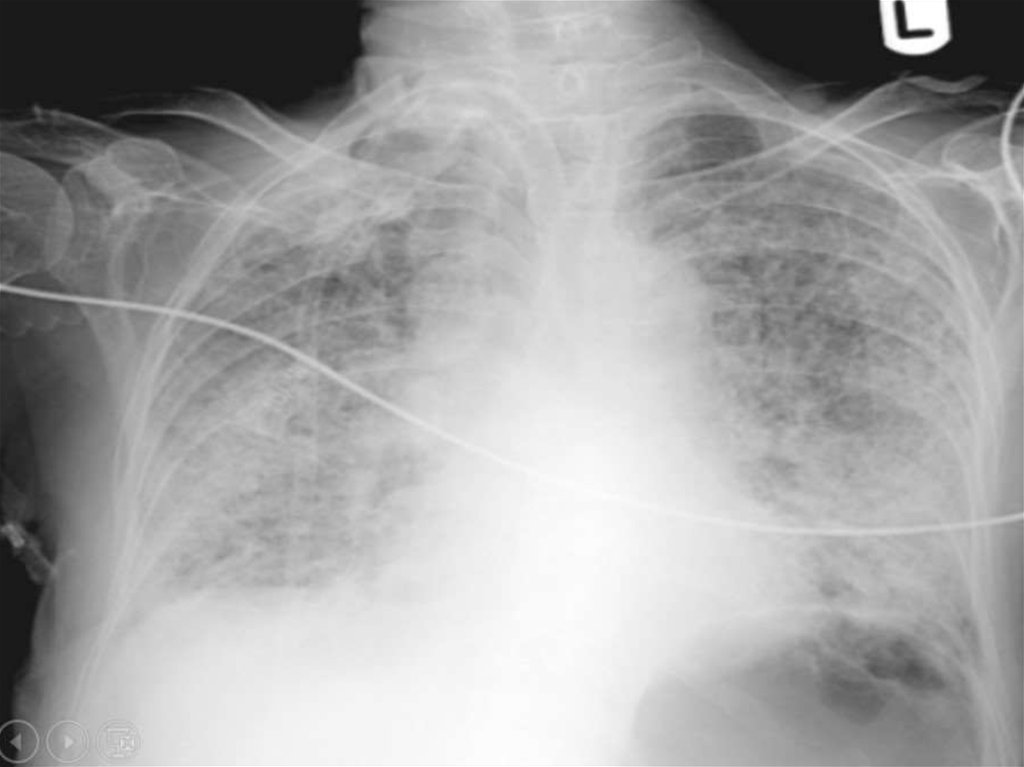

• Острый респираторный дистресс-синдром

(ОРДС) жизнеугрожающее воспалительное поражени

е лёгких, характеризующееся

диффузной инфильтрацией и

тяжёлой гипоксемией. ОРДС является частым

осложнением многих заболеваний, является

одной из важнейших проблем

анестезиологии реаниматологии